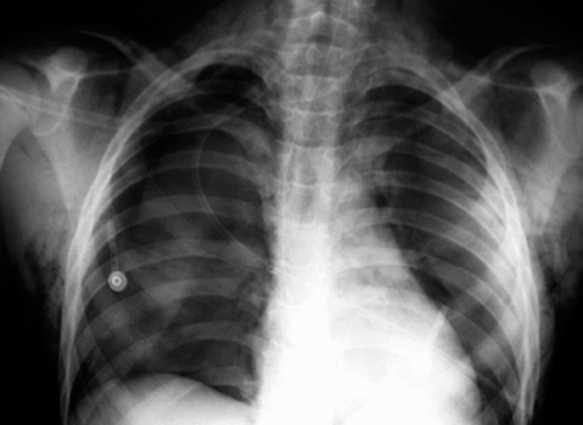

Varón de 12 años de edad, sin antecedentes personales de interés, que acudió al servicio de urgencias tras golpearse en la región cervical anterior con el manillar de una bicicleta. En la exploración física, el paciente presentaba dificultad respiratoria moderada y enfisema subcutáneo cervicotorácico que se extendía hasta el escroto. La radiografía de tórax confirmó la presencia de aire en el tejido subcutáneo y, además, puso de manifiesto un neumotórax derecho y un neumomediastino (fig. 1). Ante la sospecha de rotura de la vía aérea se realizó, a continuación, una broncoscopia flexible en quirófano y bajo anestesia general. Se observó una laceración profunda en la parte posterior membranosa traqueal de aproximadamente 2,5 cm de longitud (fig. 2). Esta lesión se encontraba a 5 cm de cuerdas vocales y a 7 cm de la carina aproximadamente. El resto del árbol traqueobronquial era normal. Dado el tamaño de la laceración y la sintomatología del paciente fue intervenido quirúrgicamente sin más demora. Se efectuó el cierre de la herida traqueal con sutura discontinua mediante un abordaje cervical anterior. Se comprobó intraoperatoriamente, mediante broncoscopia, el cierre completo de la laceración. El paciente fue extubado en el quirófano y la evolución postoperatoria cursó sin incidencias, y fue dado de alta una semana después de la intervención. La broncoscopia de control, a los 2 meses, fue normal y el paciente se encuentra actualmente asintomático con un seguimiento de 2 años.

Figura 2. Imagen broncoscópica de la laceración en la porción membranosa traqueal.